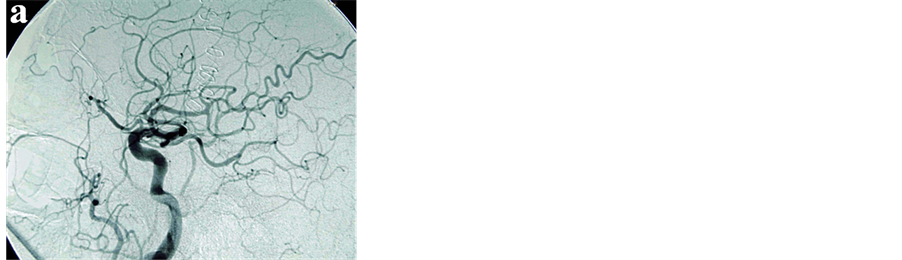

Later on, we had a chance to recheck the CT scan which had been taken 16 months previously when the patient had suffered from a right thalamic hemorrhage. It revealed that the existence of the venous pouch at the right anterior cranial fossa and that the pouch had been smaller than in the onset of the massive hemorrhage (Figure 3). Post-operative DSA showed the dAVF was completely occluded (Figure 4). The patient survived after the surgery but remained in a vegetative state.

Figure 3. CT scans without contrast medium (a), (b) obtained 16 months before showing right thalamic hemorrhage with the smaller venous pouch in the right anterior cranial fossa (arrowheads).